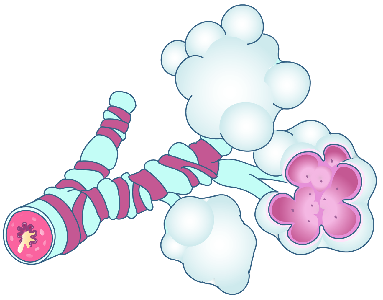

Detailreiche Fotografien aus der medizinischen Praxis ergänzen die Texte; moderne, genaue,

wissenschaftliche Zeichnungen geben Einblick in die Anatomie und die Funktion der Lunge und

anderer Organe.